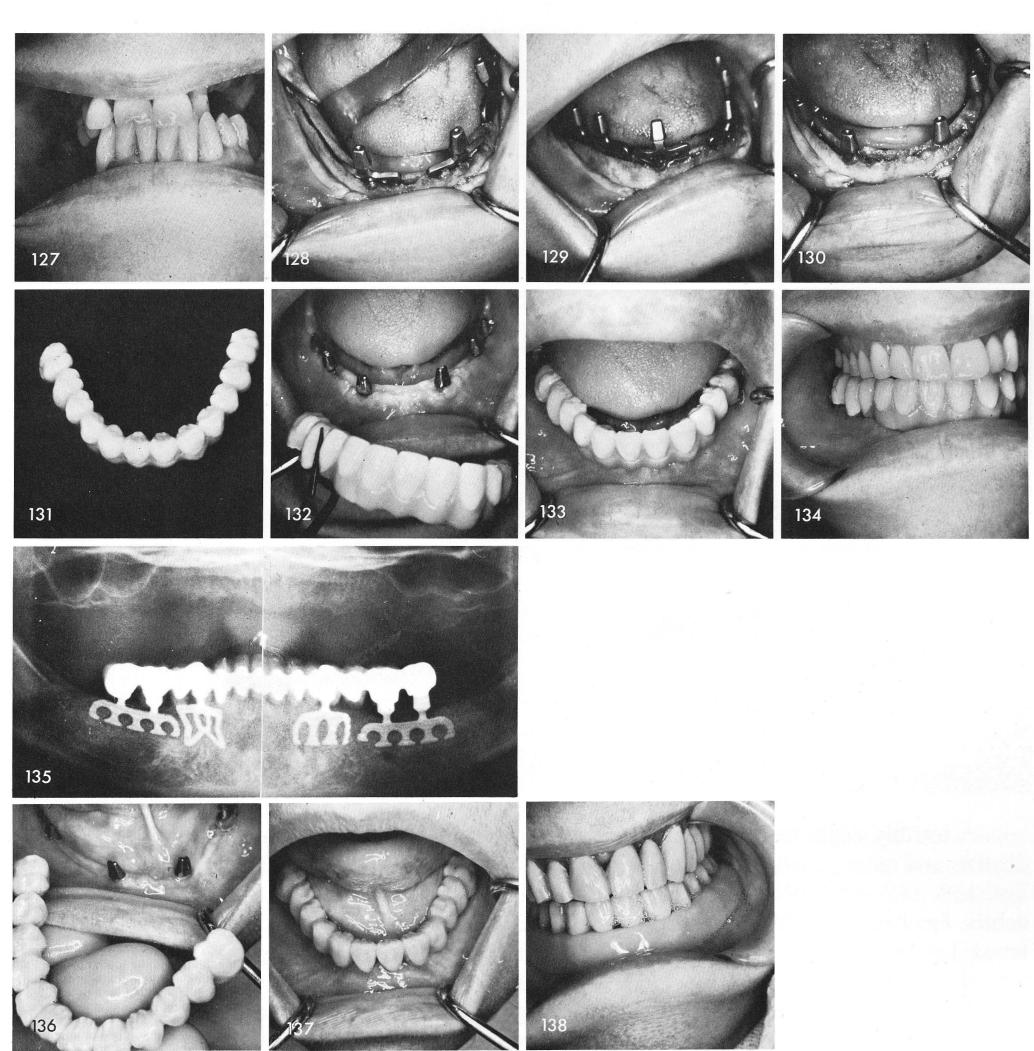

In situations where many periodontally involved teeth have to be extracted, fig. 127, leaving the mandible totally edentulous then at least six months must elapse before re-entering the area to insert bladevents, figs. 128, 129, 130. Fig. 131 shows the fabricated restoration, again with a pink gum-line. It is then fitted and cemented, figs. 132, 133, 134. The final x-ray, fig. 135.

Often only four protruding posts can be used, instead of the usual six, fig. 136, to support a full arch splint, fig. 137. In order to build out the lips a snap-on pink acrylic stent was fabricated, fig. 138, which was removed after meals.